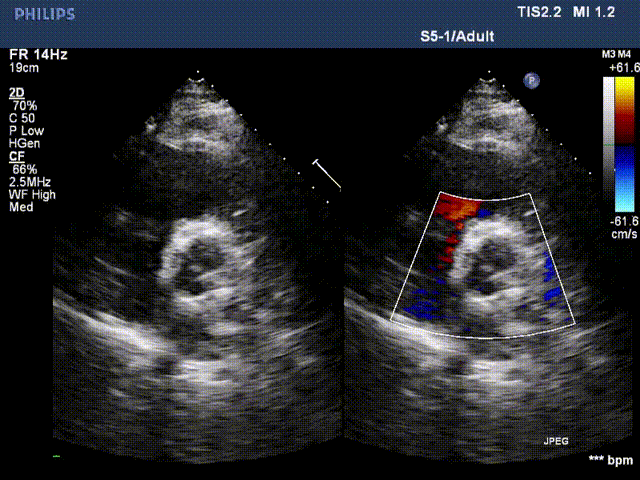

术前超声2